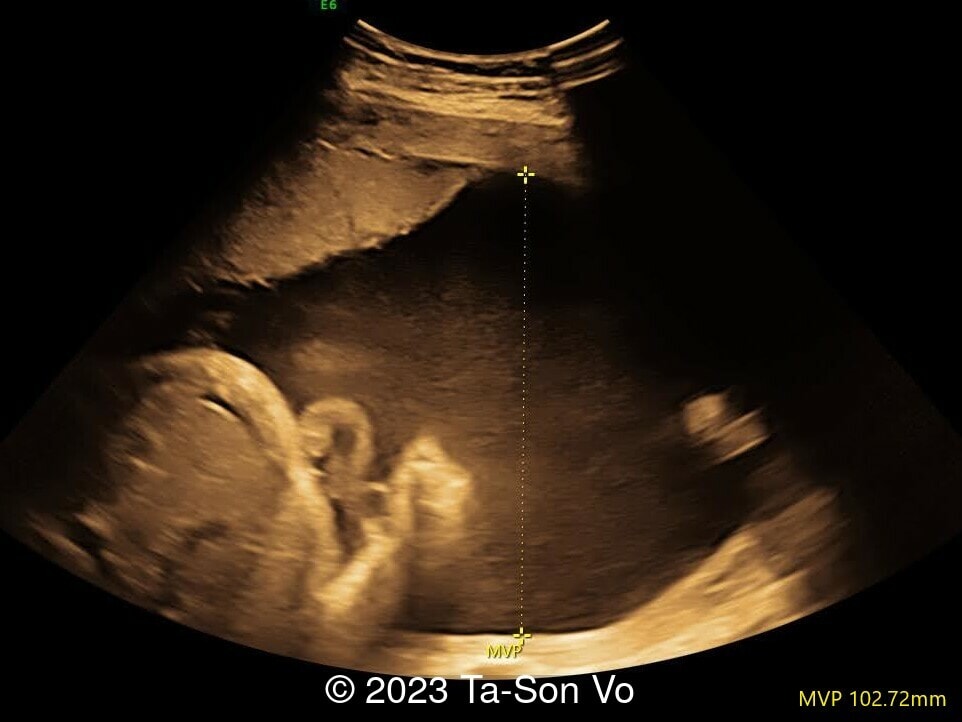

Level 2 ultrasound at 23 weeks and 28 weeks of gestation revealed thick nuchal and prenasal skin (Image 1), frontal bossing (Image 1,2), facial dysmorphism with a short nose, anteverted nostrils, flat nasal bridge, and long philtrum (Image 3,4), hypertelorism (Image 5), mega cisterna magna (Image 6) and polyhydramnios (Image 7). There was neither congenital diaphragmatic hernia nor cardiac defects with only mild tricuspid regurgitation (Image 8). Fetal biometry demonstrates a large head with rhizomelic limb shortening (Image 9).